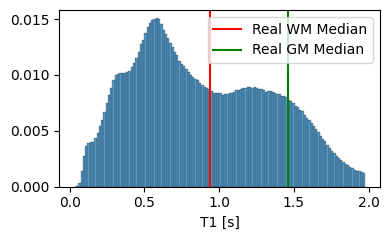

We set and based on the median of the property value distribution measured in real brain tissue [1], corresponding to a log-normal prior with a median of on T1 and a median of on T2.

3.1.2 Analysis of the Tissue Property Distribution

To ensure that our model can extrapolate to unseen modalities, it is crucial that the tissue property maps contain physically plausible values. In Figure 4, we compare the distribution of T1 and T2 values generated by our model to the average T1 and T2 values of white matter and grey matter in actual brain tissue. The results highlight the importance of the prior on the predicted T1 and T2 values, as it guides the model towards generating tissue properties that are, on average, more realistic. However, it is essential to note that the generated distribution includes tissue types beyond white matter and grey matter, such as cerebrospinal fluid and bones.